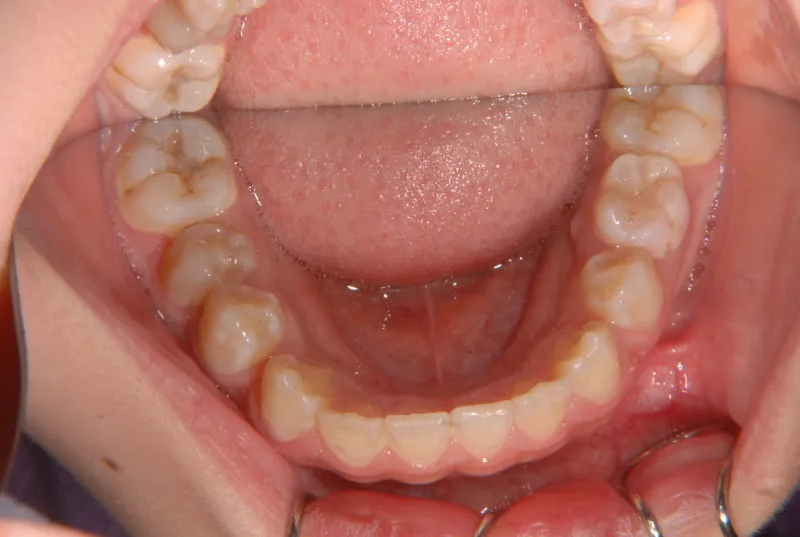

【子供の矯正(一期)】叢生・反対咬合・受け口・非抜歯症例・7歳女児【M.H様】

治療終了後

治療回数21回、2年7ヶ月の治療期間で矯正治療を終了しました。

主訴が改善され、ご満足頂きました。